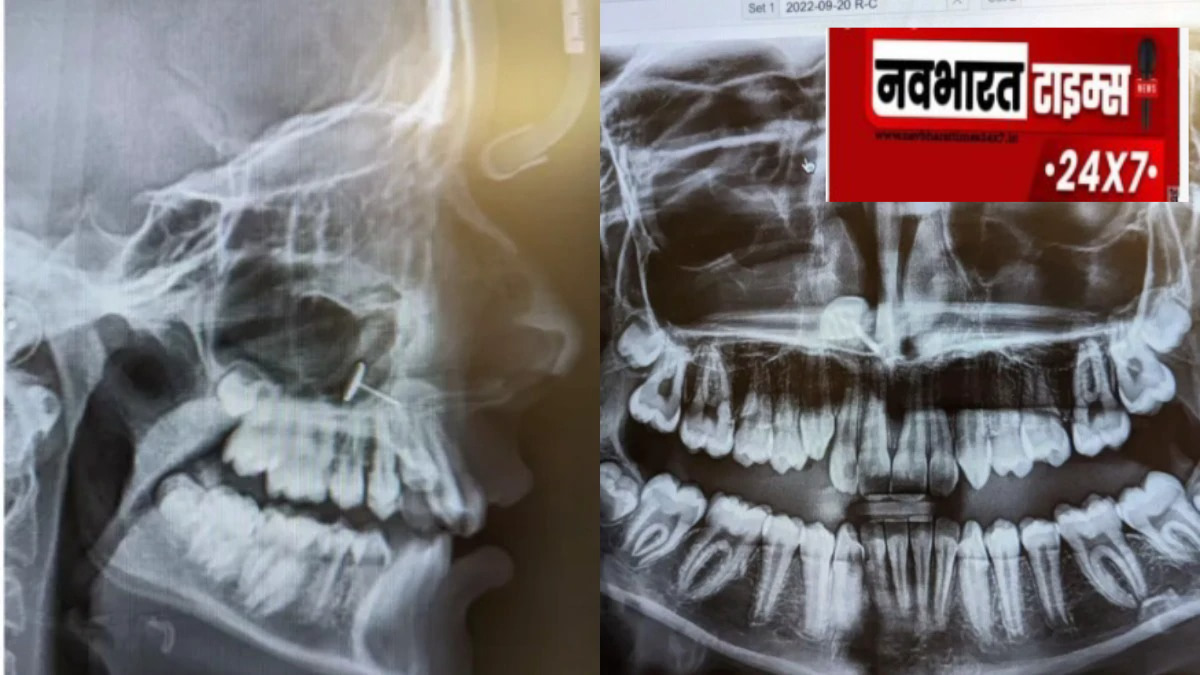

अमेरिका के वॉशिंगटन स्टेट में एक साधारण डेंटल चेकअप ने एक मां और उसकी 13 साल की बेटी के लिए एक हैरान करने वाला अनुभव